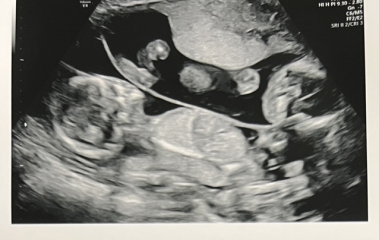

journeytomum · 26/04/2024 07:20

Hope everyone is going ok. I had a scan at 15+2 yesterday of the twins following the large sudden bleed last week. They still don't know where it came from but the twins are ok which is the main thing! I am still wiped from the pregnancy and finding it very hard going with a toddler.

Any guesses on genders from the scan pics?!

OCTOBER 2024 BABIES - Thread 4

AppleTree16 · 26/04/2024 08:54

Glad to hear it wasn’t a twin!

I think you’ve got a girl and boy there? But my nub experience is just guesswork!